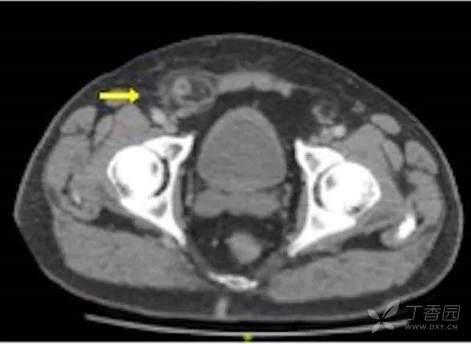

腹部CT示:阑尾增粗伴周围渗出改变,右腹股沟区条索状物,淋巴结?腹股沟疝?待排